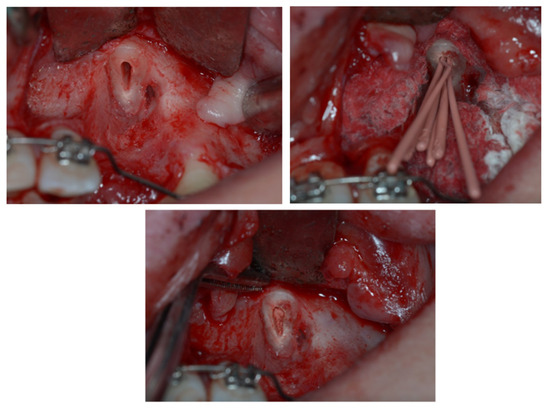

3. Therapeutic Interventions